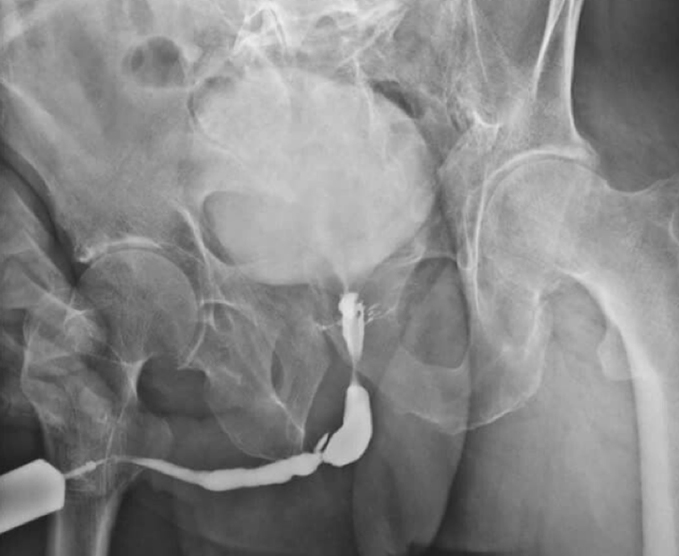

Algunos de nuestros estudios contrastados.

- Uretografía retrógrada